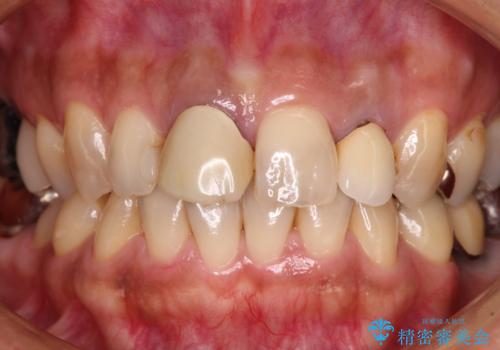

変色した保険クラウンをきれいに オールセラミッククラウンによる補綴治療

- 保険診療でのクラウンが変色してしまったとのことで来院された患者様です。

根管治療がされていなかったため、まずは根管治療を行い、その後オールセラミッククラウンにて補綴することとしました。

左上の歯も歯肉縁部分にメタルの色が見えており、合わせて治療することをお勧めしましたが、今回は1歯のみを治療することとしました。